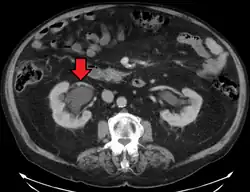

Stone causing hydronephrosis[16]